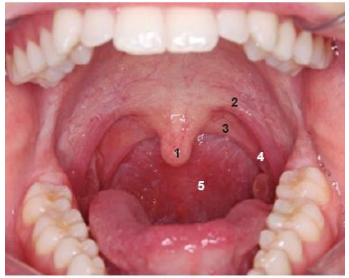

O palato mole contém músculos e tecido fibroso revestidos por mucosa. Durante a deglutição, o palato mole se eleva, evitando a entrada de alimento na parte nasal da faringe. Na fonação, ele pode elevar-se mais ou menos, causando um velamento total ou parcial da boca em relação à parte nasal da faringe, a depender do tipo de som emitido (som nasal ou vocálico)

Levando em consideração a estrutura bucal, analise a imagem e estabeleça a relação com a denominação e número:

A sequência CORRETA é: